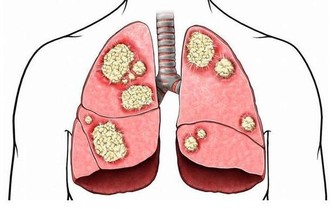

然而現在研究已經證實,服用複合維生素並不能保護你免受心臟病、中風或死亡的影響。大量研究支持這一結論。

基本上,沒有確鑿證據表明服用複合維生素會降低患慢性疾病的風險,或以任何方式保護你的健康,甚至美國心臟協會也不建議服用它們。當然,你真的有維生素缺乏症,那就另當別論。